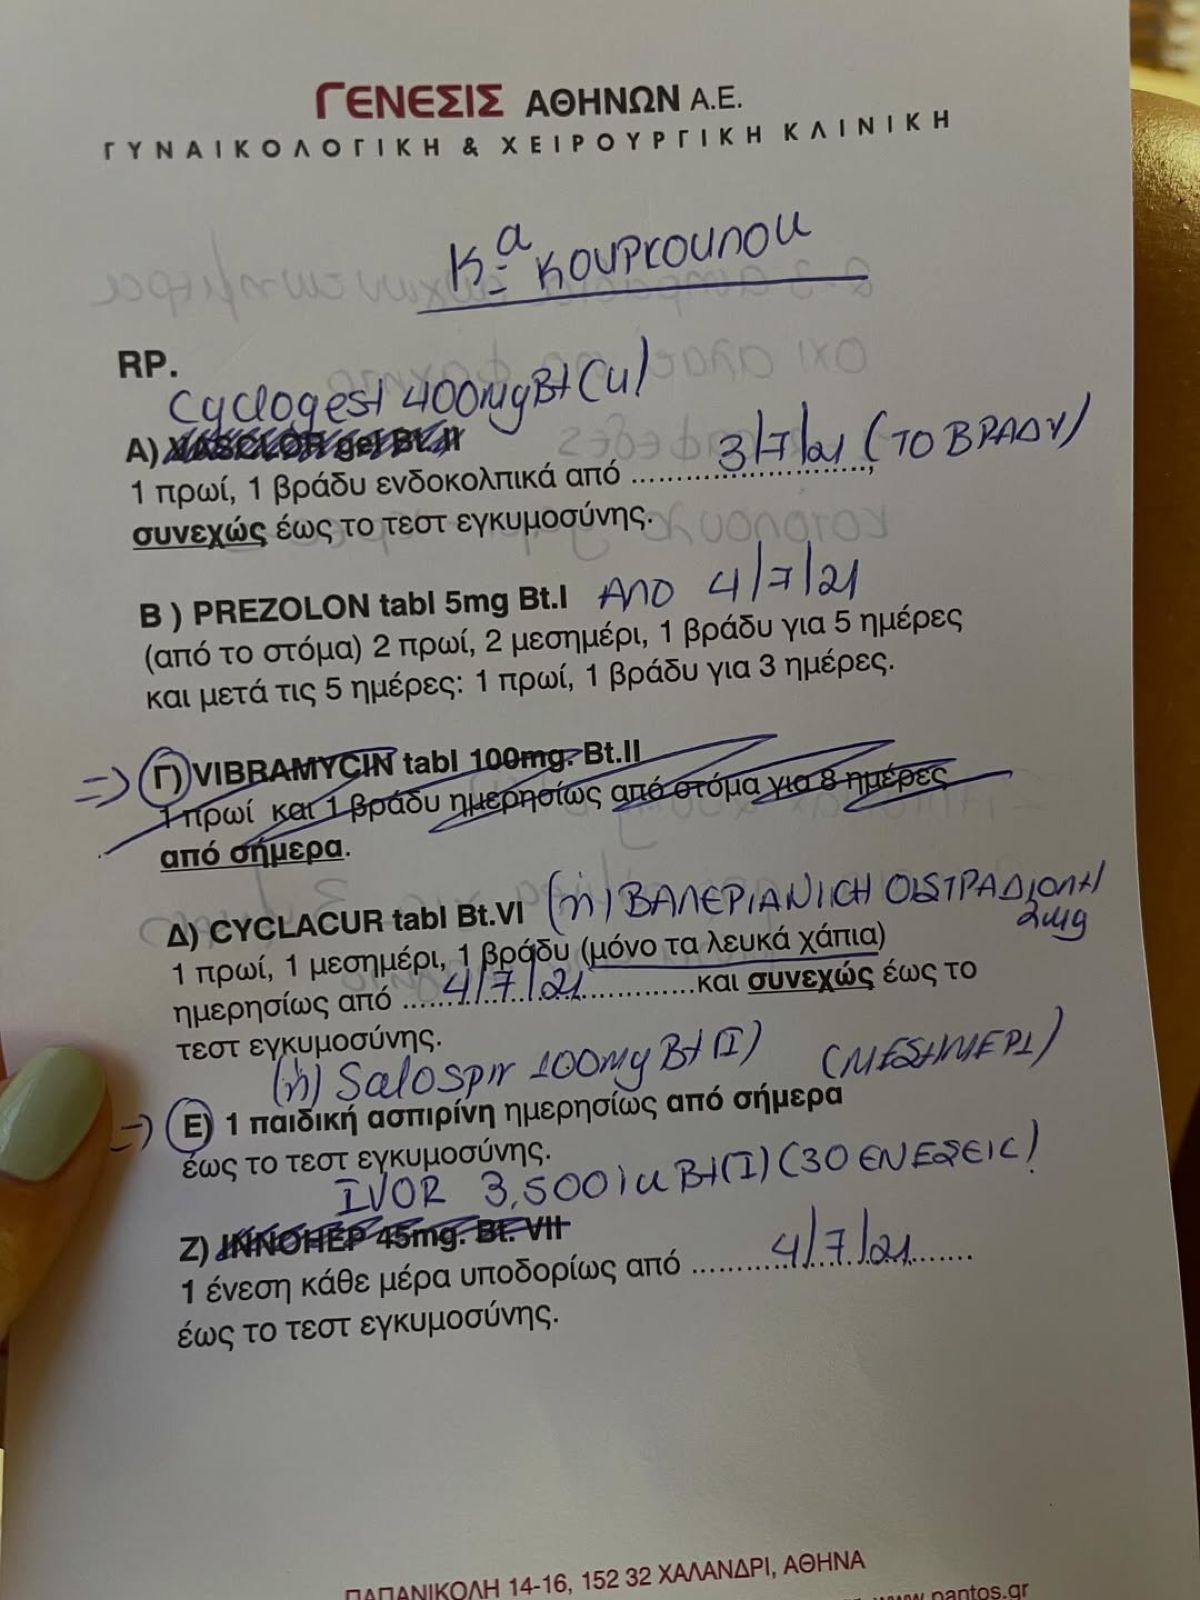

Η Εριέττα Κούρκουλου λοιπόν, έγραψε χαρακτηριστικά: «Η ιστορία σου ξεκινάει πολύ πριν το πρώτο σου κλάμα. Ξεκινάει από την αγάπη. Την αγάπη δυο ανθρώπων που ενώ βρίσκονταν στον κόσμο τους έπεσαν ο ένας πάνω στον άλλον και τελικά αποφάσισαν ότι ήθελαν να κάνουν μαζί ένα παιδάκι. Εκεί αρχίζει το καλό! Προσπάθεια, αποτυχίες, κλάμματα, αγκαλιές, προσευχές, εξετάσεις, γιατροί, χάπια, ενέσεις, απογοήτευση, ελπίδα, έμβρυα και μεταφορά ενός εκ των δώδεκα στις 8 Ιουλίου του 2021.

Αυτό το ένα ήσουν εσύ! Στις 21 Μαρτίου ήρθες και έφερες τα πάνω κάτω και εδώ και τέσσερα χρόνια εκεί παραμένουν – τα ΠΑΝΩ – ΚΑΤΩ! Όταν σου δώσαμε το όνομα των παππούδων σου φοβόμουν μην σε επισκιάσει. Πού να ήξερα τι μας περίμενε… Ένα παιδί ευφυέστατο σε βαθμό που μας τρομάζει, με αρκετά νεύρα, (σπάνιες) αγκαλιές που σε παραλύουν και μια καρδία από χρυσάφι. Ευχαριστώ για τις στιγμές, τα άπειρα μαθήματα και το όνειρο που έκανες πραγματικότητα. Συγγνώμη για τα λάθη που έχω κάνει και εκείνα που θα κάνω στο μέλλον. Υπόσχομαι να σε αγαπάω με όλο μου το είναι για πάντα! Χρόνια Πολλά ★ μου!».